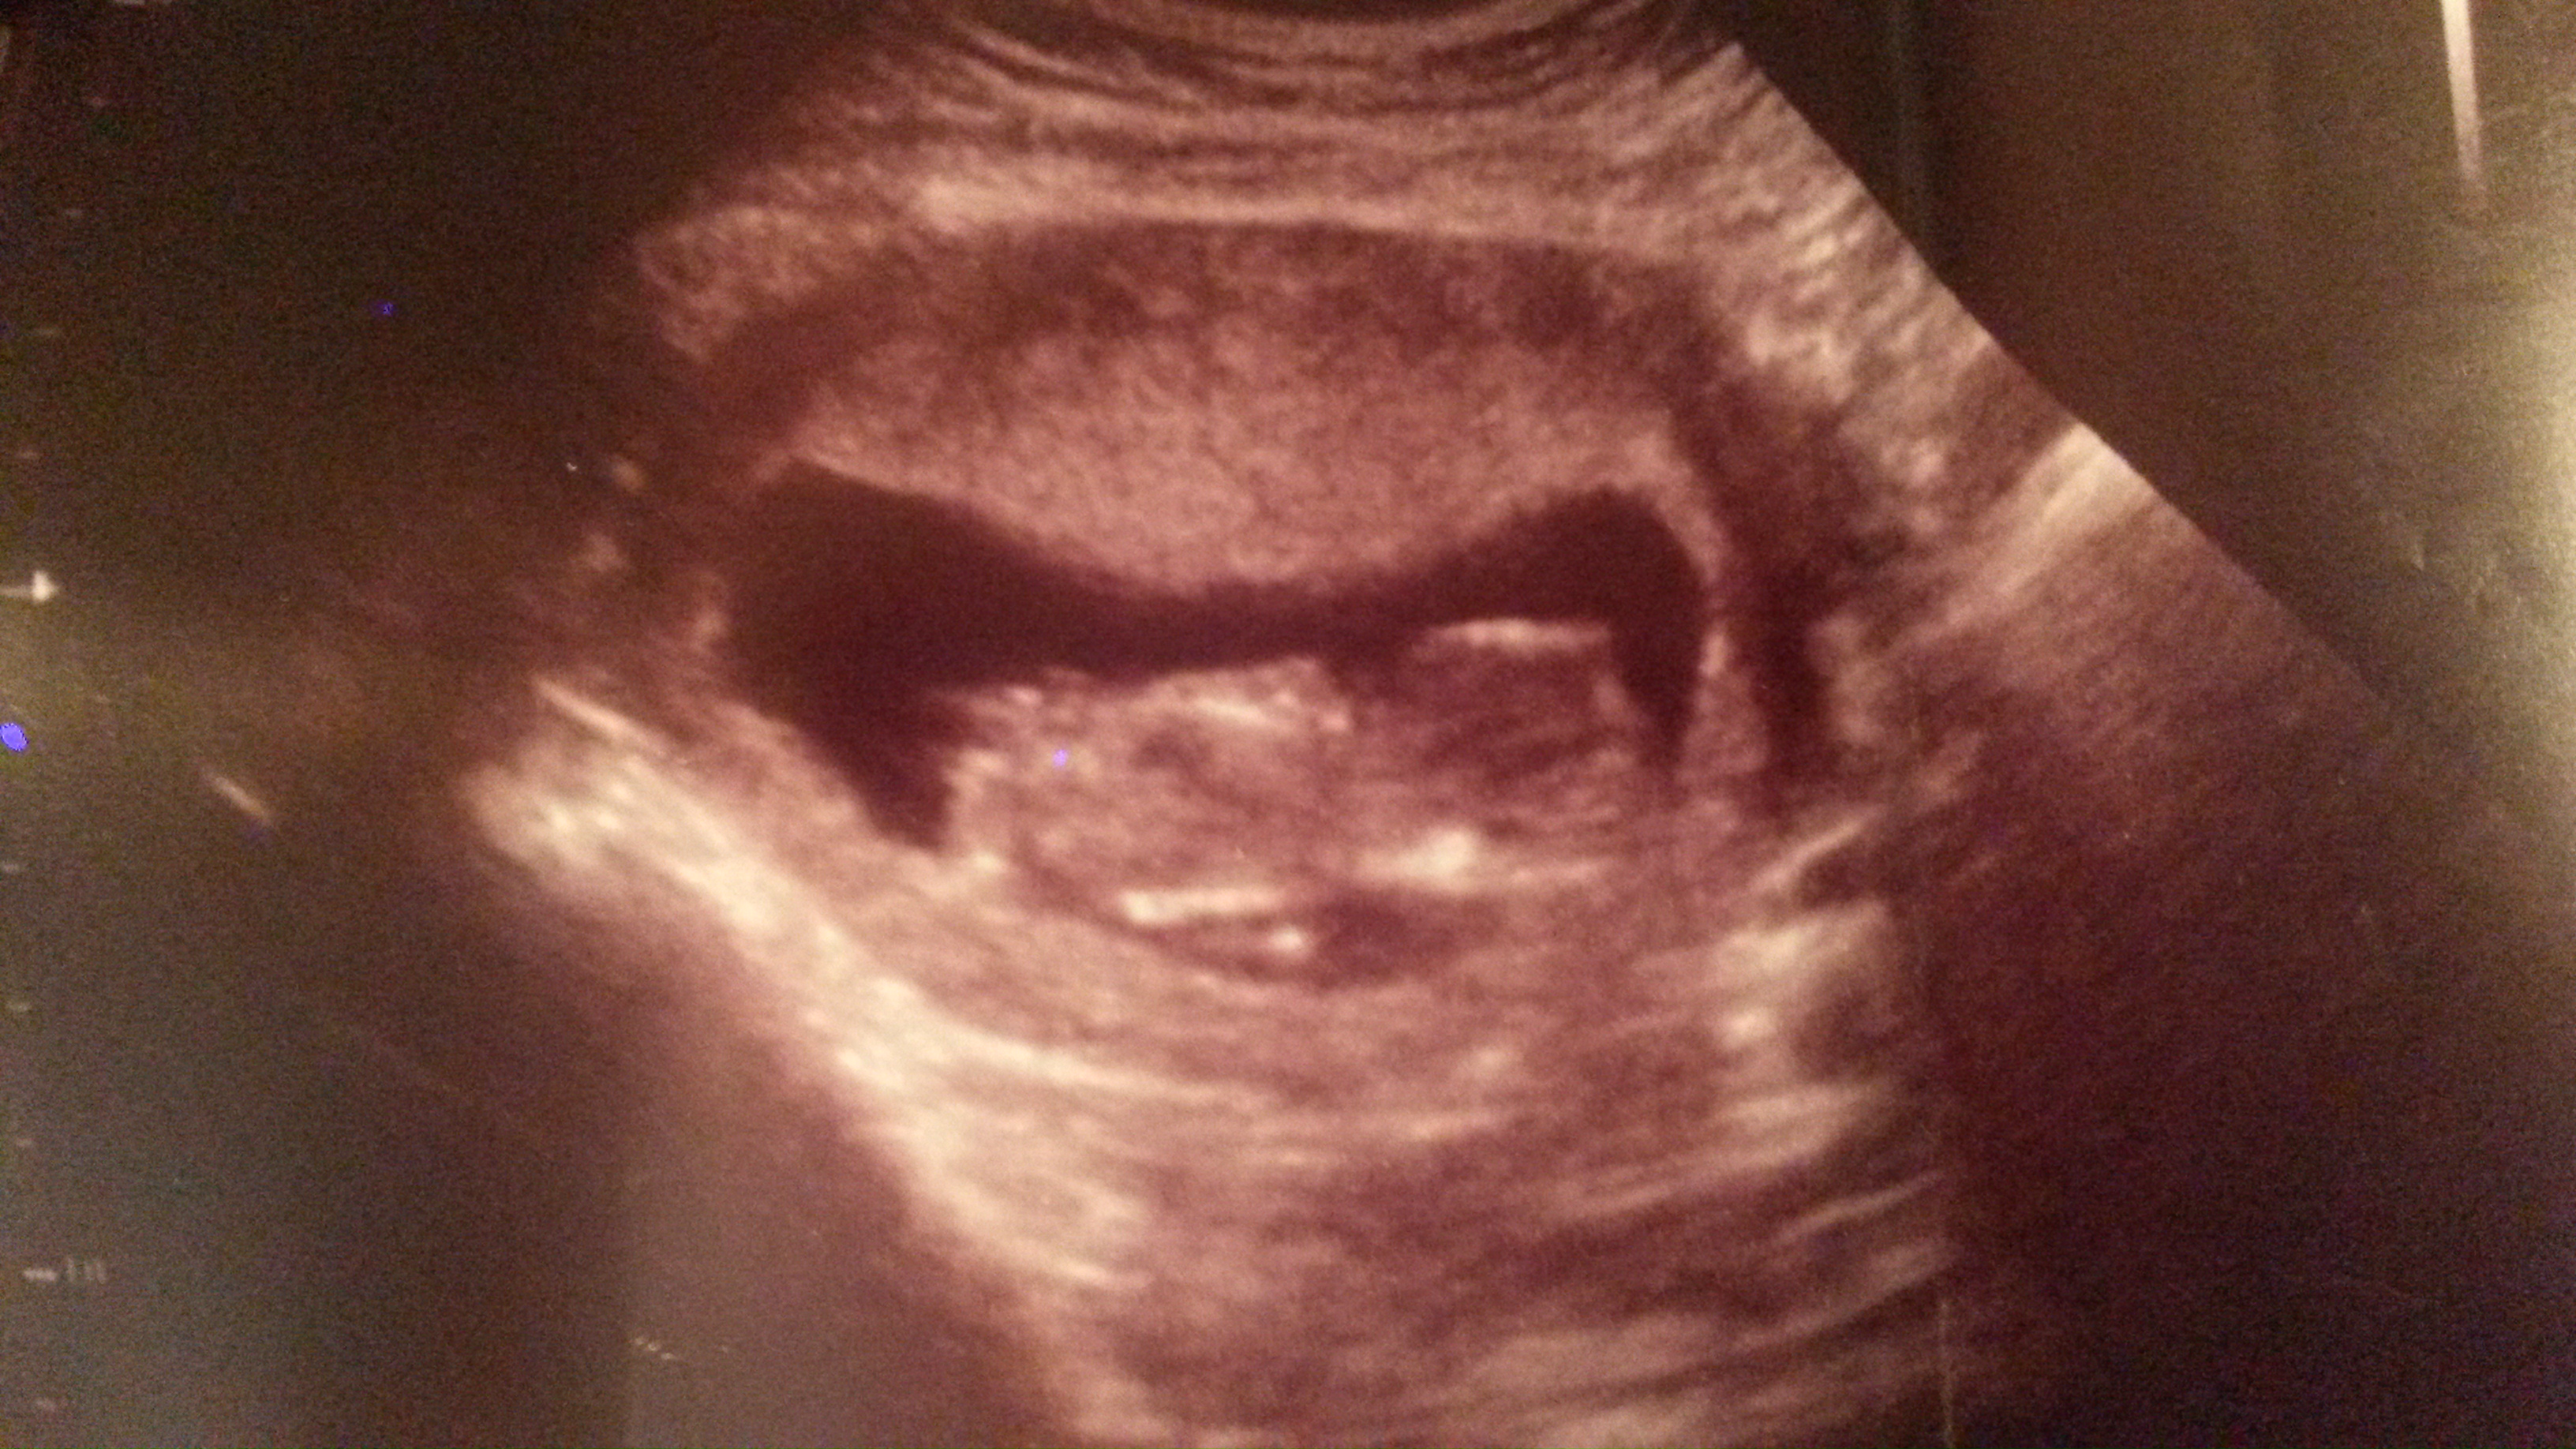

12 weeks 4 days what you all you ladies think :)

Attachment 20203

Maybe boy??

I don't think I see the nub